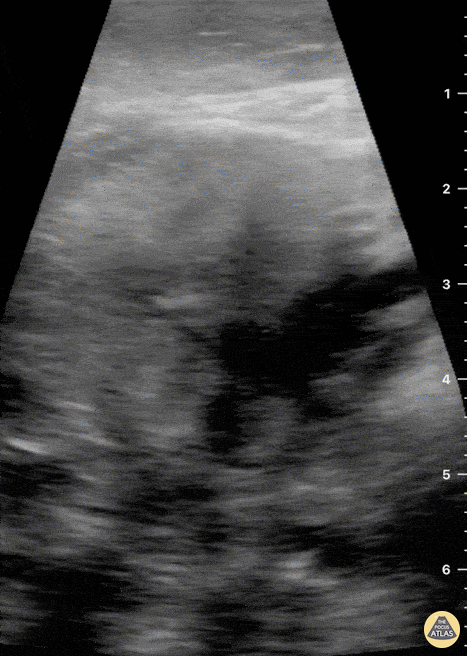

Not your classic Blunt Neck Trauma: Submandibular Gland Fragmentation A closer look to the right submandibular gland reveals a deep end with heterogeneous borders. There is also significant edema and free fluid invading deeper structures. Dr. Felipe Urriola & Dra. Daniela Gallardo. Emergency Unit, Puerto Aysen Hospital. Chilean Patagonia